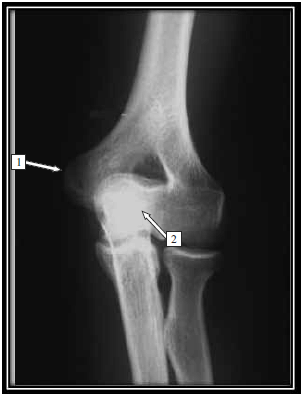

Observe a imagem.

Na radiografia do cotovelo em AP, as estruturas sinalizadas são, correta e respectivamente,